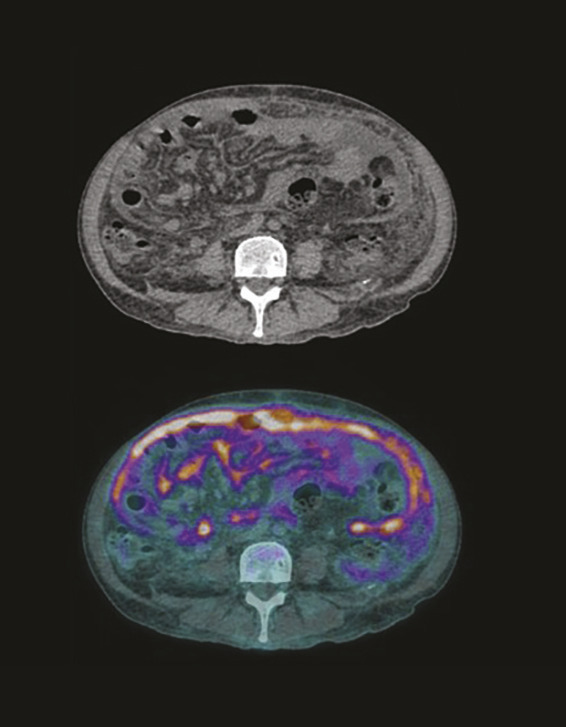

Cet homme de 67 ans était hospitalisé pour décompensation œdémato-ascitique. La tomodensitométrie abdomino-pelviennne montrait un foie cirrhotique avec thrombose portale, ascite abondante et péritoine épaissi prenant le contraste.1 Les leucocytes sanguins oscillaient entre 5 et 12,7 G/L, avec lymphopénie variable et protéine C-réactive à 100 mg/L. Des ponctions d’ascite itératives montraient la présence de lymphocytes et de monocytes avec des neutrophiles inférieurs à 250/mm3. L’examen microscopique direct et les cultures d’ascite étaient non contributifs. Le gradient d’albumine sérum-ascite était élevé (> 11 g/L).2 Le taux d’adénosine déaminase (ADA) était peu élevé (27 UI/L, normale < 24).2 La tomographie par émission de positons au fluorodésoxyglucose (fig. 1 et 2 ) montrait une fixation intense et diffuse du péritoine épaissi (flèches vertes) et des adénopathies hypermétaboliques abdominales et thoraciques (flèches rouges). La cœlioscopie montrait un péritoine multinodulaire. Les biopsies révélaient des granulomes épithélioïdes et gigantocellulaires avec nécrose caséeuse. Mycobacterium bovis était identifiée par tubage gastrique.